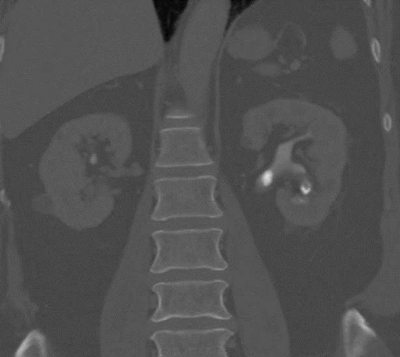

Stone fragility

CT can be used to assess the internal structure of calculi, which is best seen using bone windows [4] compared with abdominal windows where the stone may appear homogeneous. Some studies have shown that heterogeneous calculi are more fragile leading to better fragmentation with treatment, as the irregularities seen within the calculus act as focal spots for shock wave treatment, leading to better fragmentation of the stone [5] (Figure 3).

Figure 3a: Abdominal windows stone fragility.

Figure 3b: Bone windows stone fragility.